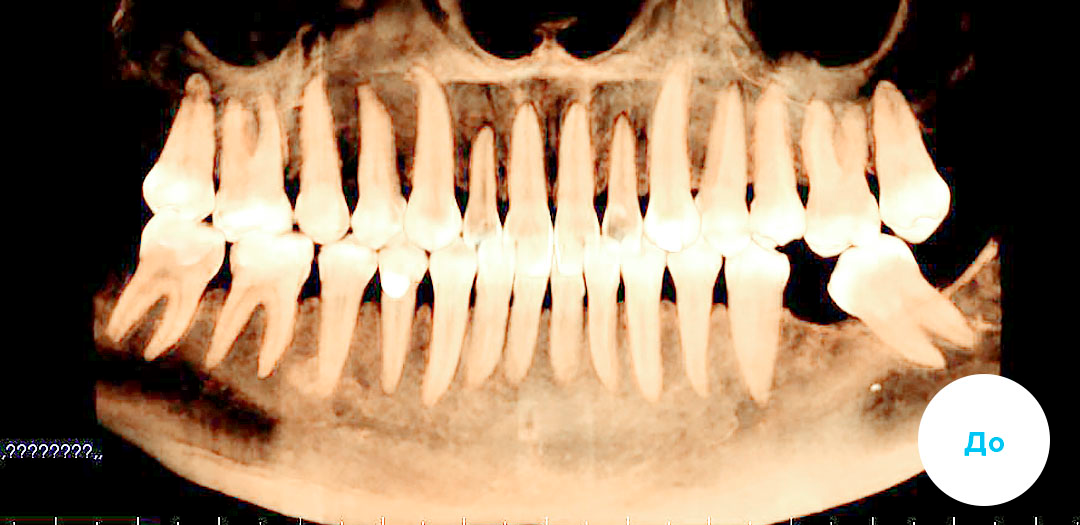

В приведенном клиническом случае ортодонты использовали мини-имплант и цепочки.